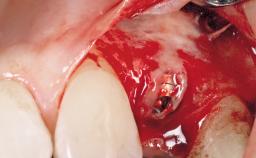

Immediate Flapless Placement of an Implant in a Maxillary Left Central Incisor Site

A 42-year-old female patient was referred to our clinic at the School of Dentistry of the University of São Paulo in November 2004, presenting a deficient restoration in the upper left central incisor. The clinical examination revealed no gingival retraction or any signs of gingival inflammation and, therefore, previous periodontal treatment was not considered. The patient presented a high lip line at full smile and a thin tissue biotype. This combination characterized a high-risk situation from an anatomic point of view, which required careful preoperative planning and cautious surgical execution.

Placement Protocol Immediate implant placement

Socket Morphology Single-root socket

Socket Integrity Sufficient, with intact bone walls